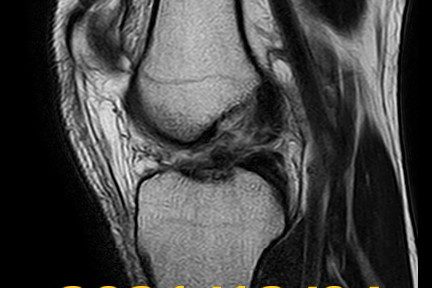

2021年12月3日、カバディという競技の練習中に、左膝を捻った。同日に、病院でMRI検査を行い、以下のように診断された。

左膝前十字靭帯断裂

MRIの画像診断では、自然治癒の傾向が見られるものの、はっきりとした靭帯の連続性は確認できなかった。帰国後は、競技の練習をせず、運動療法のみを行い、靭帯の回復を待った。2022年5月19日、三回目のMRI検査を行った。

三回目のMRIの画像診断では、前回とほぼ同じく、はっきりとした靭帯の連続性は確認できなかった。徒手検査での、膝関節の動揺性は減少しており、前十字靭帯断端の後十字靭帯等への癒着が考えられた。